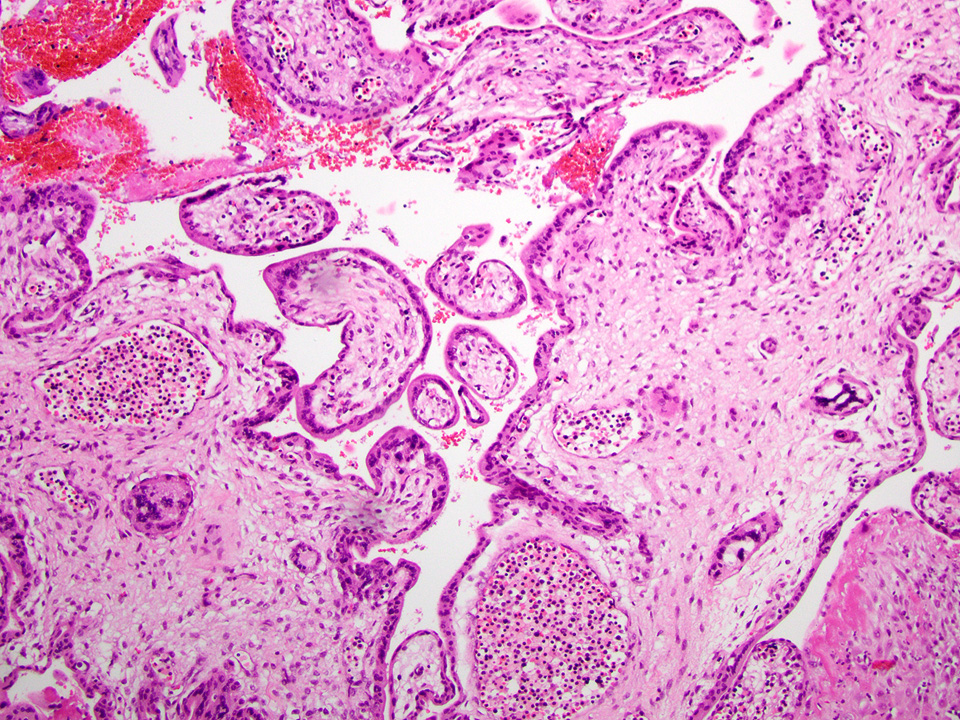

Differential diagnosis

- Hydatidiform mole (Int J Gynaecol Obstet 2021;155:86, Hum Pathol 1998;29:505, Hum Pathol 1996;27:708):

- Complete mole:

- Gestational trophoblastic disease characterized by diffuse hydropic enlargement of chorionic villi with associated trophoblastic hyperplasia

- Distinguishing features

- Uniformly enlarged chorionic villi

- Marked and often circumferential trophoblast proliferation, both cytotrophoblastic and syncytiotrophoblastic

- Loss of the normal nuclear p57 staining in cytotrophoblasts and villous stromal cells; therefore, p57 immunostain is often helpful in distinguishing complete mole (absence of the normal pattern of staining in chorionic villi) versus edematous villi (normal pattern of staining with nuclear staining in villous cytotrophoblasts and stromal cells

- Partial mole:

- Gestational trophoblastic disease characterized by an admixture of normal and enlarged chorionic villi with irregular contours and mild trophoblastic hyperplasia

- Distinguishing features

- Chorionic villi of different sizes

- Mild focal to circumferential, syncytiotrophoblastic hyperplasia

- Scalloped villous outlines

- Trophoblast inclusions

- Excess tissue grossly

- Retained normal p57 staining pattern; therefore, p57 immunostain will not distinguish a partial hydatidiform mole from a nonmolar gestation

- Flow cytometry for ploidy analysis; partial hydatidiform moles are nearly always triploid (Mod Pathol 1995;8:775, Hum Pathol 2000;31:914)

- Distinguishing features

- Aneuploid nonmolar conceptions can be challenging to distinguish from a partial mole because of overlapping histomorphology but can be differentiated from a partial hydatidiform mole by carefully searching for partial mole features as described above

Microscopic (histologic) images

Contributed by Chrystalle Katte Carreon, M.D. and Drucilla J. Roberts, M.D.